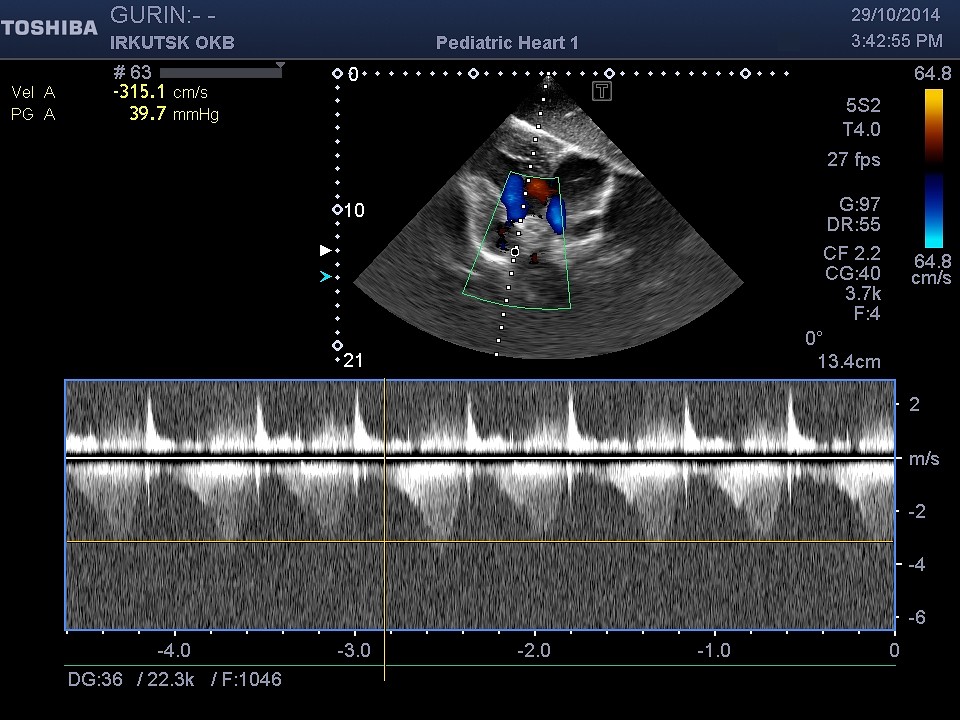

ЭхоКГ

29.10.14 (Литаш ИВ): единый желудочек с параллельным ходом сосудов, ДМПП до 10 мм. PG

на бандинге ЛА 89 мм.рт.ст., MG 42 мм.рт.ст. Недостаточность митрального клапана 3

степени. (см. запись на диске).